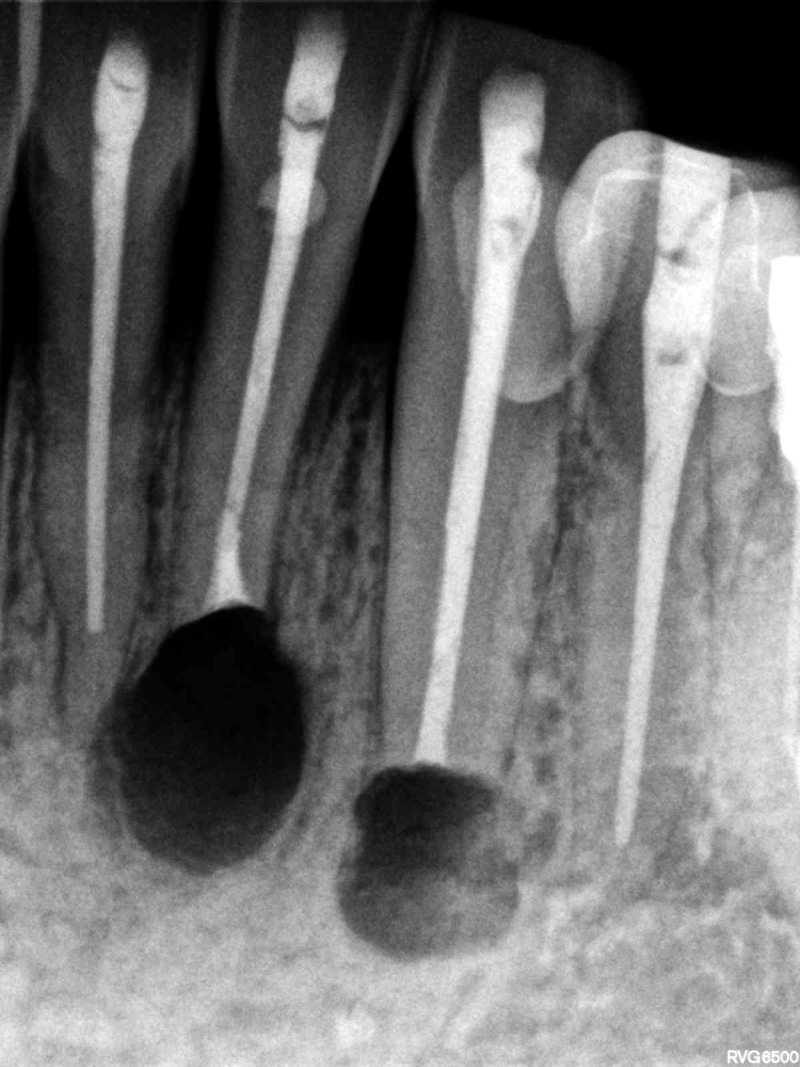

Inicio Especialidades Endodontia